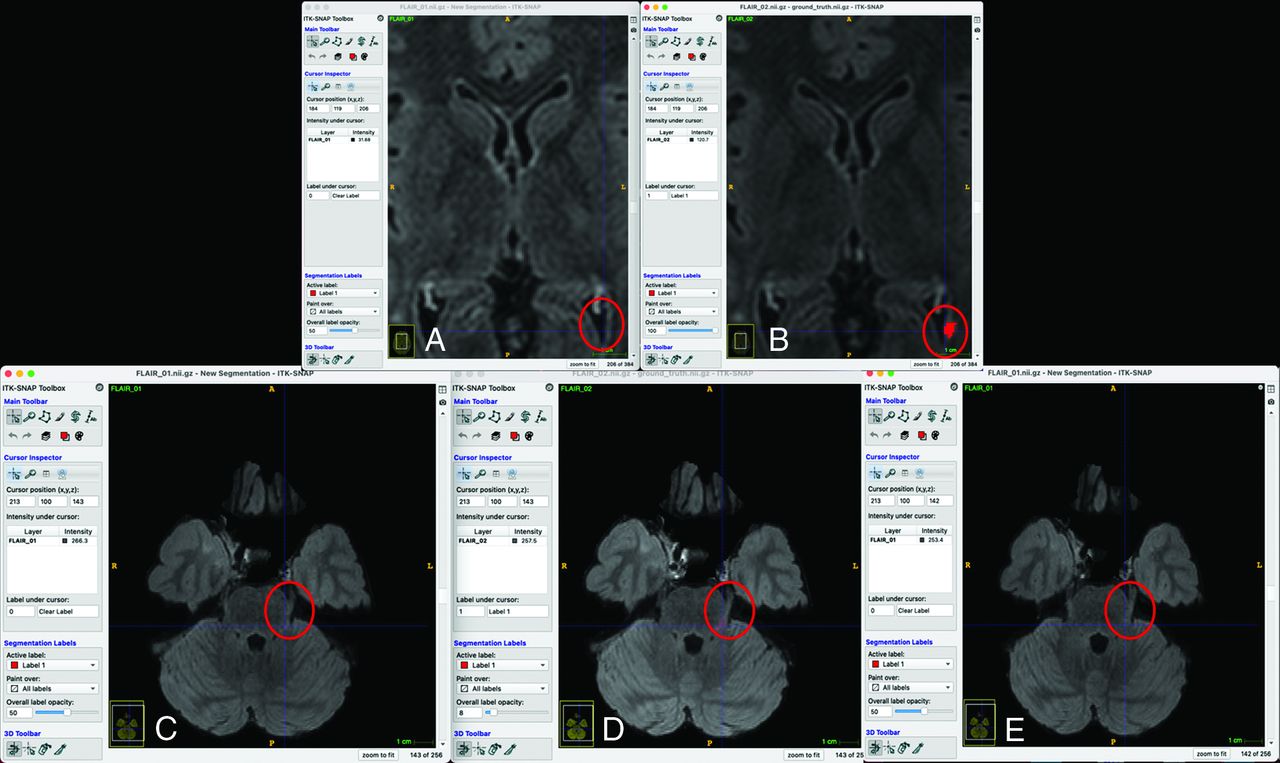

Failure analysis on external validation showed that in many instances, a potential cause for misclassified cases was misregistration of images rather than the machine learning model. For example, of the 3 false-negatives, 2 were likely related to misregistration (Fig 6).

False-negative analysis (A and B, Upper row, C–E, Lower row). Two of the 3 false-negative cases in the external validation set are shown. A and B, The new lesion map falls within the ventricle on the prior image, making a negative prediction more likely because the low gray levels were associated with negative predictions (Fig 4). C, D, and E, The orientation of the proximal left trigeminal nerve is different so that the segmentation is cast onto the normal brainstem instead.